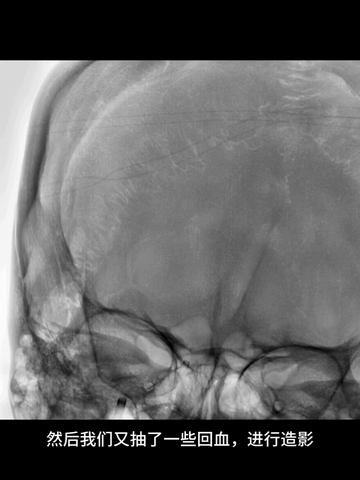

透视下,利用支架锚定作用,将中间管头端推至ICA末端;而后中间管接50ml注射器(血管钳辅助下,保持负压状态),回撤取栓支架同时前送中间管,直至其头端达M1远端。

撤出取栓支架后,负压状态下缓慢回撤中间管,直至海绵窦段时才见回血通畅;此时见支架取栓和导管抽吸取出大量红色血栓。